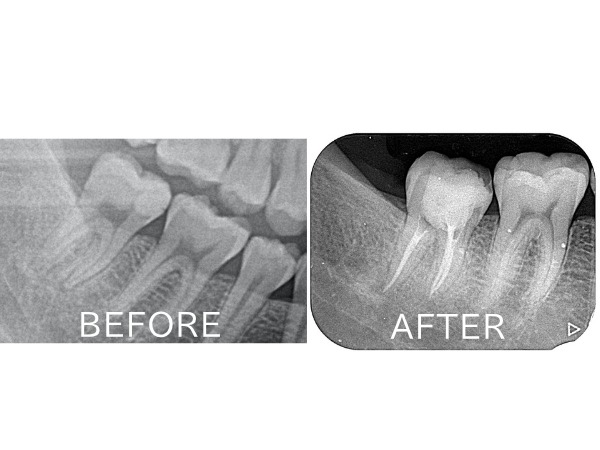

こちらが初診時のレントゲン写真になります。

レントゲン写真を見ると、以前治療した詰め物(コンポジットレジン)がかなり神経まで近接していることが分かりました。おそらく非常に大きな虫歯治療を数年前にしたものかと思われます。

また、レントゲン写真を細かく見ると、詰め物の下に黒い影があり、虫歯になっていることも分かります。昔の詰め物の隙間から虫歯が再発し、細菌が神経に到達してしまったことで、歯の神経が炎症を起こしている状態です。歯科用語では歯髄炎という状態になり、自発痛(ズキズキした痛み)が出てしまっているので、残念ながら神経を取る治療(抜髄)が必要となります。